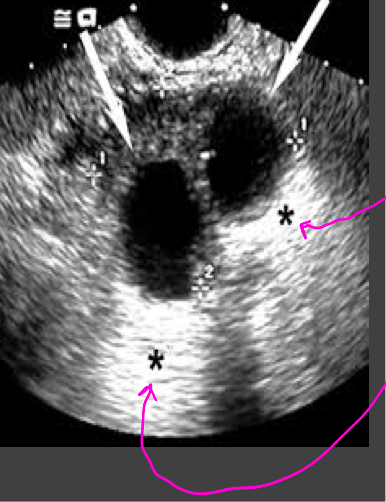

Artifacts-enhancement

Acoustic enhancement- sound travels through fluid uninterrupted, so the echoes deep to a fluid collection are brighter than the adjacent tissue

In poorly attenuating objects such as a cyst, the echoes returning from regions deep to the object are of higher amplitude

Artifacts- shadowing

A structure that blocks the sound wave causes acoustic shadowing (gallstones)

Strongly attenuating or highly reflective surface, the returning echoes posterior to the structure are decreased in amplitude